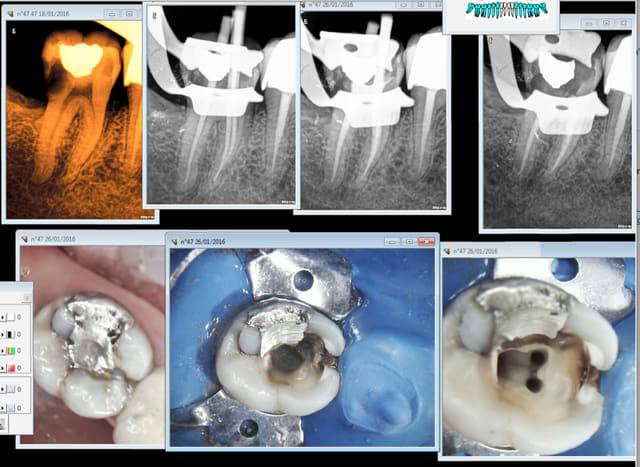

47 a symptomatique. Sur traitement ? -)

Capture d e cran 2016 01 26 17.54 - Eugenol